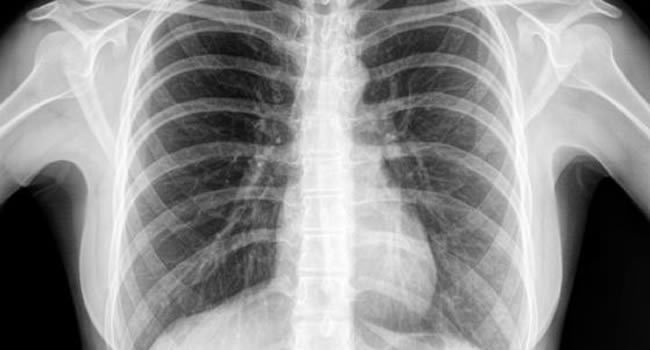

Οι ακτινογραφίες πραγματοποιούνται με πλήρως ψηφιακό εξοπλισμό και όχι ψηφιοποιημενο από έμπειρους Τεχνολόγους – Ακτινολόγους με άδεια ασκήσεως Επαγγέλματος.

Ο πιο σύγχρονος φορητός Ακτινολογικός εξοπλισμός πλήρως ψηφιακής απεικόνισης (DR) σε μια κινητή ακτινολογική μονάδα, μπορεί να επισκεφθεί τον ασθενή οπουδήποτε στην περιοχή της Θεσσαλονίκης και των περιχώρων και να σταλεί, αν ο ασθενής το επιθυμεί, η γνωματευμένη ακτινογραφία ηλεκτρονικά μέσω διαδικτύου στον θεράποντα- παραπέμποντα ιατρό ο οποίος θα λάβει το αποτέλεσμα στο προσωπικό του υπολογιστή, tablet, Smartphone οπουδήποτε κι αν βρίσκεται.

Άμεση παράδοση της ακτινογραφίας και της γνωμάτευσης λίγα λεπτά μετά την άφιξη της ακτινολογικής μονάδας. Δυνατότητα επανάληψης της ακτινογραφίας για την παραγωγή του βέλτιστου αποτελέσματος, εξαιτίας της ψηφιακής αυτόματης εμφάνισης της ακτινογραφίας που γίνεται στην οικία του ασθενούς